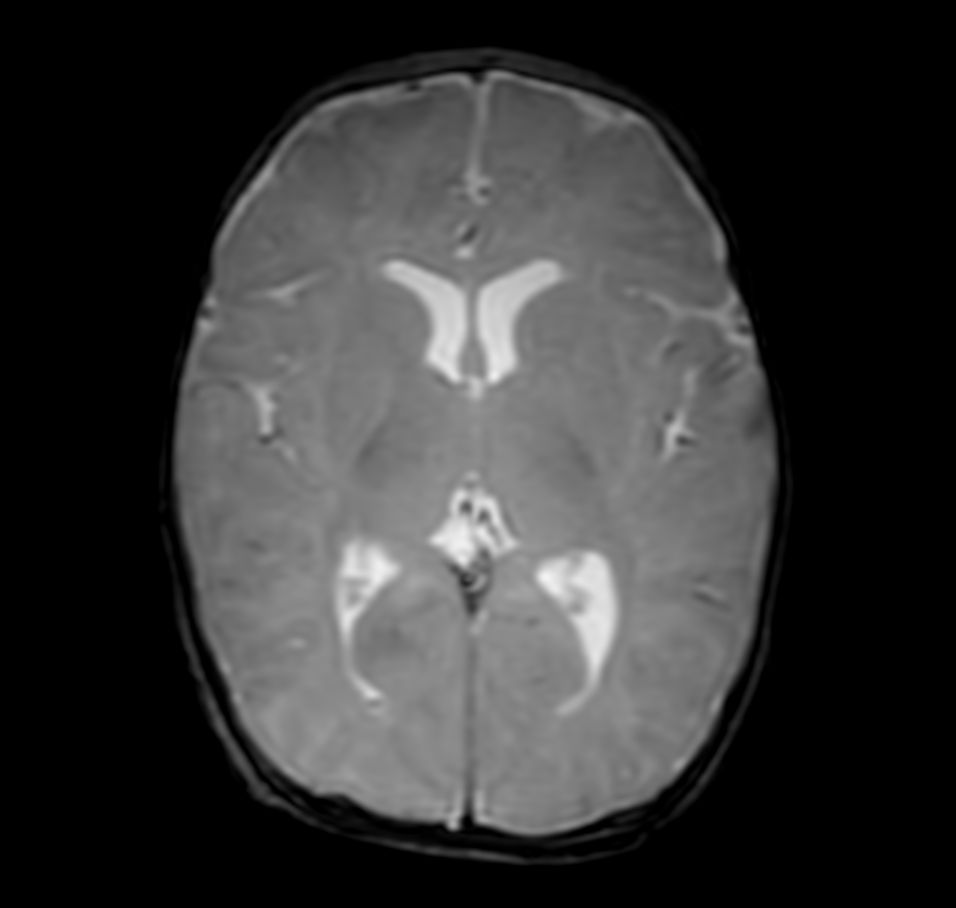

Axial T2w TSE with ComforTone